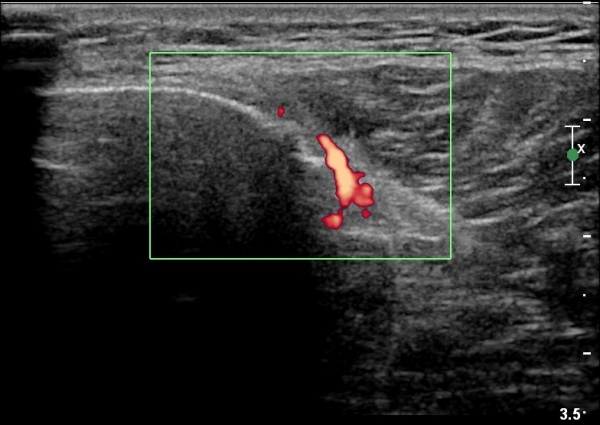

[¹«¸­] °æ°ñ ÇǷΰñÀý ÃÊÀ½ÆÄ¼Ò°ß(sonographic findings of stress fracture of tibia)

±º´ë¿¡ ÀÔ´ëÇÏ¿© ÈÆ·ÃÀ» ¹ÞÀº º´·ÂÀÌ Àִ ȯÀÚ´Â ¾à 2ÁÖ ÀüºÎÅÍ ¹ß¸ñ ºÎÀ§ÀÇ ÅëÁõÀÌ ÀÖ´ø Áß

ÃÖ±Ù¿¡´Â ¹ß¸ñ À§ ¾Æ·§´Ù¸®¿¡ ÅëÁõÀÌ ¹ß»ýÇÏ°í ½ÉÇÏ°Ô °ÉÀ¸¸é ½ÉÇØÁö´Â ¾ç»óÀÓ

¾Æ·§´Ù¸® Áß°£ ºÎÀ§¿¡ °æ¹ÌÇÑ ¿¬ºÎÁ¶Á÷ ºÎÁ¾ÀÌ °üÂûµÇ°í ¾à°£ÀÇ ±¹¼ÒÀû ¾ÐÅëÀ» º¸ÀÓ.

ÃÊÀ½ÆÄ °Ë»ç

¹Ì¼¼ÇÏ°Ô ¿¬ºÎÁ¶Á÷ ºÎÁ¾°ú °¡°ñ Çü¼ºÀÌ °üÂûµÊ.

Bilateral stress fracture of the tibia diagnosed by ultrasound. A case report

https://www.ncbi.nlm.nih.gov/pmc/articles/PMC3558228/pdf/main.pdf